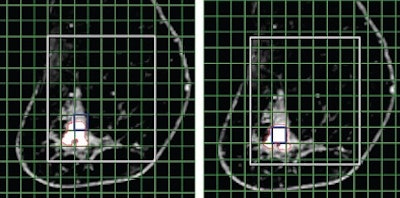

| MR images of invasive ductal carcinoma in a 62-year-old woman. Both images show how shifting MR spectroscopic imaging voxels can be performed retrospectively in all three spatial dimensions to allow improved matching with the pathologic area. Images courtesy of Radiology. |